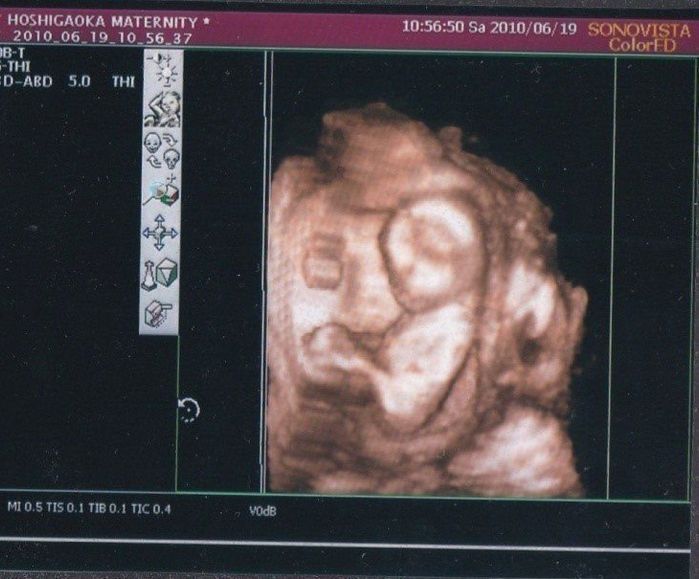

こちらは最初で最後の4D写真です。頭が上の方にあり左の方に向かって写っているのが脚です。脚を曲げて座っている形にみえます。4Dで見る我が子が楽しみだったのですが、残念ながらこちらを向いてはくれませんでした。